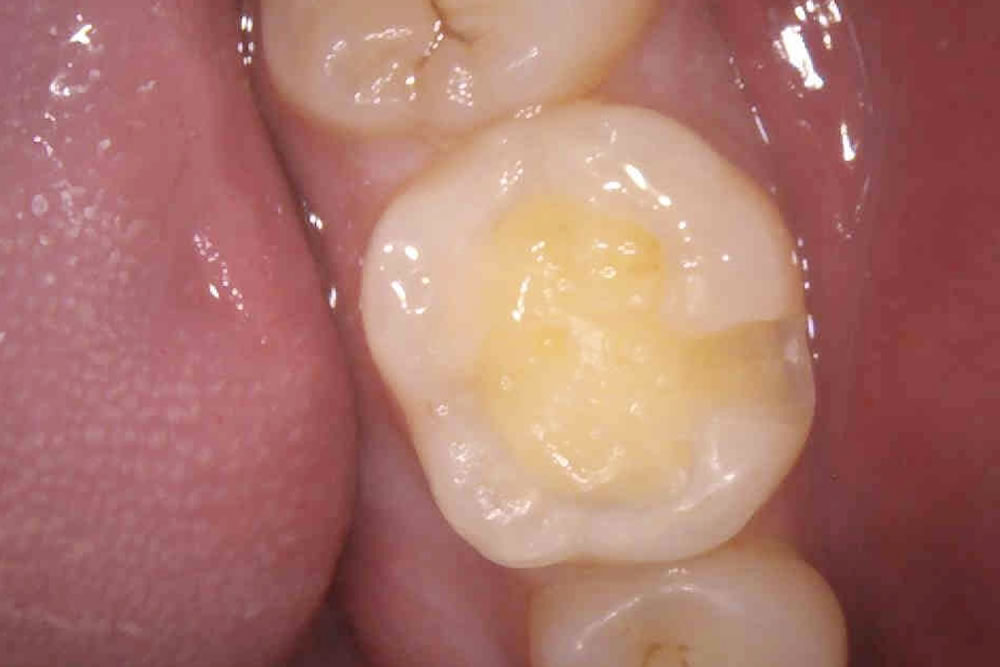

二次むし歯を治療後にハイブリッドインレーで修復した症例

自覚症状はありませんでしたが、過去に他院で治療をしたレジンの溝から二次むし歯が確認できたため、治療をすることになりました。

ハイブリッドインレーの装着

歯の切削範囲が大きかったため、二次むし歯のリスクが低いハイブリッドインレーを被せて治療完了となりました。

術後は問題なく噛むことができ、機能的にも審美的にも大変満足していただけました。現在はむし歯の早期発見、早期治療のため、定期的なメインテナンスで通院いただいています。